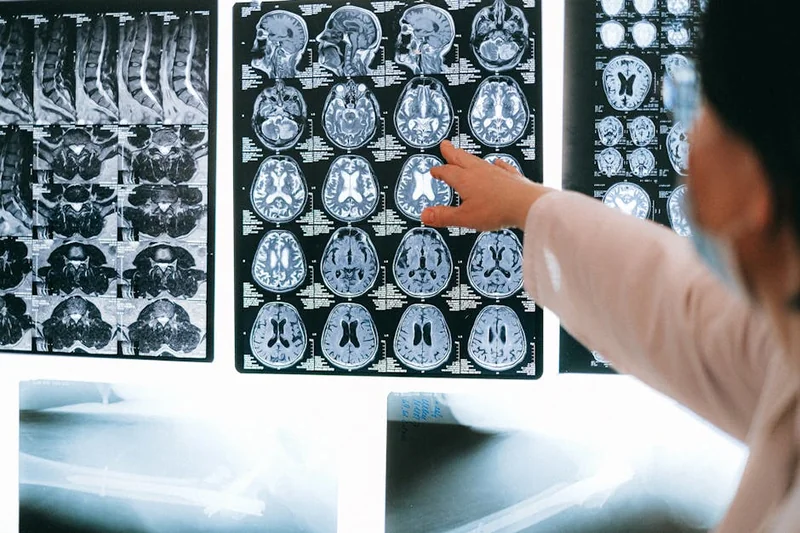

뇌파의 변화는 어떻게 측정되는가?

뇌파의 변화는 EEG(뇌파 검사)를 통해 측정됩니다. 이 과정을 통해 뇌의 다양한 상태와 활성화를 관찰할 수 있습니다. 임사체험 동안의 뇌파 패턴을 분석하면, 그 상태에서의 인식과 감정의 변화를 이해하는 데 도움을 줍니다.